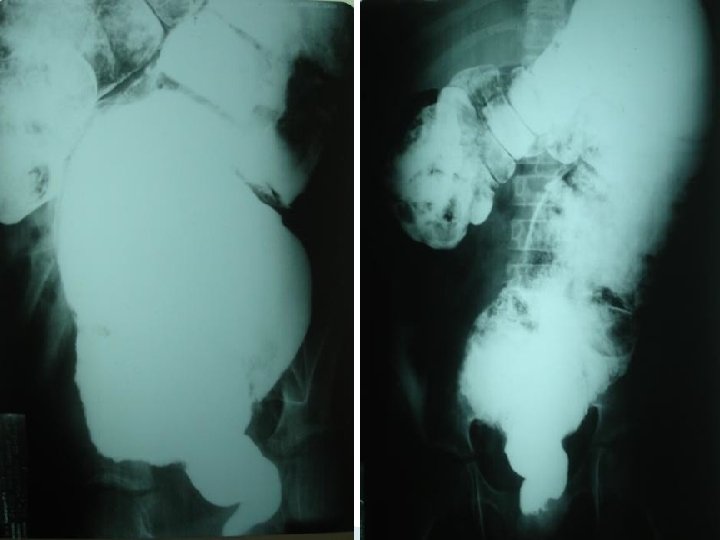

Rotação Intestinal Incompleta Diagnóstico: O diagnóstico deve ser feito com auxílio de exames radiológicos; Poderá ser pedido trânsito intestinal e/ou clister opaco; Poderá ser observado mau posicionamento do duodeno, do cólon ou imagem de espiral no caso dos volvos;

Rotação Intestinal Incompleta

Megacólon congênito Doença de Hirschsprung Diagnóstico radiológico: A radiografia simples de abdome evidencia distensão de alças com ausência de ar nos segmentos distais, na maioria dos casos. O enema baritado, obrigatoriamente realizado sem preparo de colo, e com as radiografias tardias de 24, 48, 72 e até 96 horas, classicamente revela imagem de “cone de transição”, geralmente ao nível do retossigmóide, que separa o segmento espástico de intestino agangliônico da zona dilatada a montante;